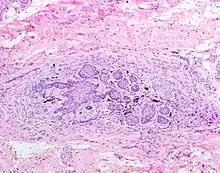

![]() The juxtaoral organ of Chievitz is composed of nests of benign squamoid epithelium closely associated with multiple nerve bundles. The deep location and squamous appearance can histologically mimic invasive squamous cell carcinoma. (Hematoxylin and Eosin stained section, 100x magnification) | |